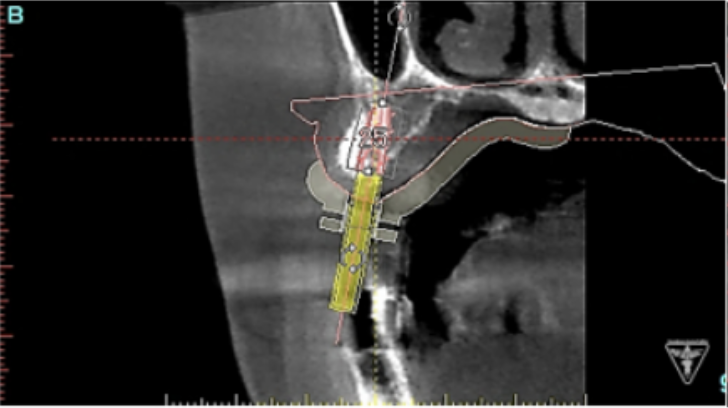

サージカルガイドの作成

インプラント埋入前のCTによる確認